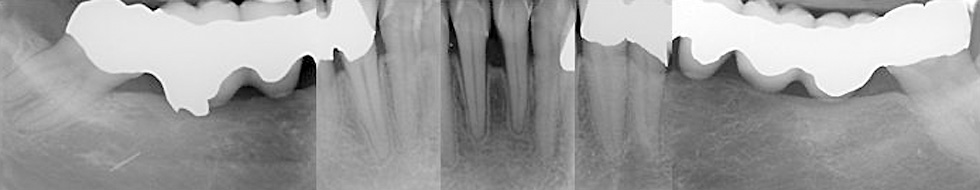

Abb. 1a: Röntgenstatus vom 14. Juli 2009

Der komplexe Fall

Abb. 1b: Röntgenstatus vom 14. Juli 2009

Abbildung 1: Radiologisch liegen folgende Diagnosen vor: Insuffiziente Wurzelfüllungen an 18,17,21,26, Beherdung an 21, zervikale Karies an 17,11, enge Wurzelproximität an 18,17, Tiefer intraalveolärer Knochendefekt an 25,26.